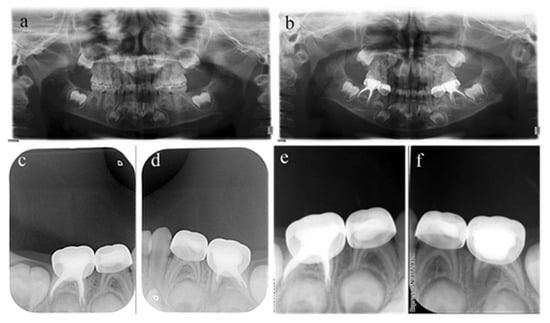

Figure 2.

#75 and #85 were treated with pulpectomies under DGA with a 17-month follow-up period (42-month-old female child). (a) Preoperative panoramic radiographic showed no periapical radiolucency. (b) Two weeks later, the postoperative radiographs showed optimal filling in both teeth; (c) Nine months after treatment, the radiograph showed nothing abnormal in #85. (d) Nine months after treatment, the filling paste in the root canal of #75 showed partial resorption. (e) Seventeen months after treatment, the radiograph showed nothing abnormal in #85. (f) Seventeen months after treatment, the filling paste in the root canal of #75 was completely resorbed. Radiolucency was seen around the mesial root as well as pathological root absorption. The pulpectomy in #75 failed but succeeded in #85.